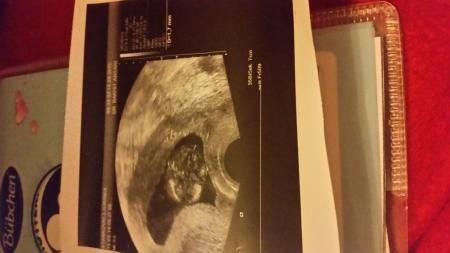

Hallo bin heute in der 13+1ssw da ich am Donnerstag starke blutungen bekommen habe musste ich heute wieder zu meiner fä sie hat dann ultraschall gemacht und meine beim Baby ist NT 1,7 mm das soll ja nichts heißen hab am Donnerstag ein Termin zur feindiagnostik habe angst ab welchen Wert sollte man sich sorgen machen Bitte um Antwort Danke im voraus

Ja hat sie ich hab auch ein Bild bekommen

Da ist das Bild

Bild zu

Die NT ist absolut unauffällig!!!!!!!